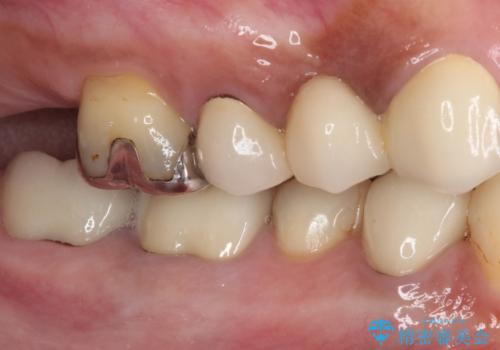

- 歯を削る量が少ないとの触れ込みで最近接着ブリッジを装着したものの、そのブリッジと歯の間に隙間ができているとのことで来院された患者様です。

歯の裏側を一層だけ削り、接着力に頼ったブリッジを装着してはみたものの、案の定咬む力に負けて、接着が剥がれてしまっていました。

歯を削る量は増えますが、より長い期間再治療なく使用していただくことを最優先に考え、フルカバレッジのオールセラミックブリッジにて補綴することとしました。

他にも、奥歯の銀歯の下にもむし歯が多くあり、痛みが生じていたため、根管治療などを行った上で、オールセラミッククラウンにて補綴治療することとしました。